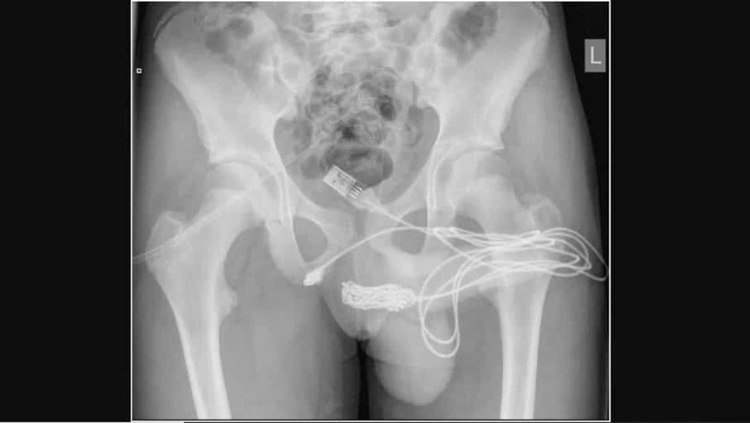

O incidente ocorreu em Londres, na Inglaterra e a identidade do jovem não foi revelada.